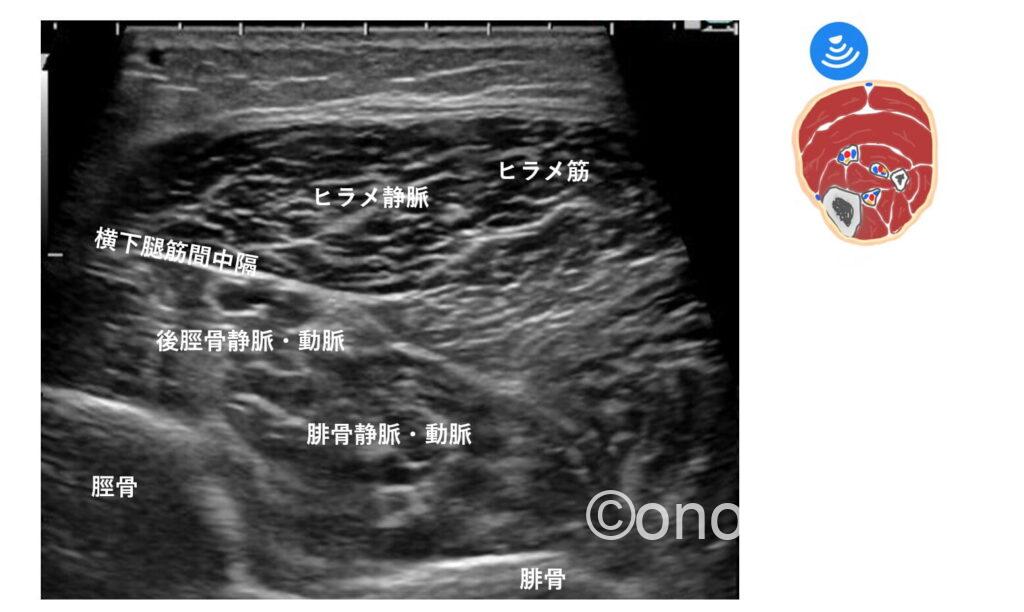

横下腿筋間中隔(TIMS)というヒント

TIMSは、浅層にあるヒラメ筋と、深層にある長母趾屈筋(FHL)や長趾屈筋(FDL)の間に介在する線維性の組織です。

文献によると、後脛骨動脈がTIMSへの直接的な血流供給源(栄養血管の供給元)となっているため隣接して走行しているとの事。

後脛骨動脈と静脈は並走しているので(動脈を挟んで静脈が2本走行している)TIMSに隣接している静脈・動脈→後脛骨静脈・動脈として認識出来るのではないかと思います。

個人的には、脛骨とヒラメ筋の間を滑るように走行している血管のイメージです。